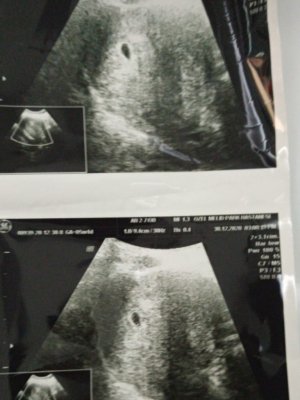

İlk ultrason resimlerinizi paylaşın ramzi teorisine göre cinsiyeti tahmin edeyim bakalım tutacak mı?

Siftahı ben yapayımBu 6+5 görüntüsü ikizler. Doktor ilk fotograftakine yorum yaptı ama diğerine yapmadı. Ikisi de karından

Bence kiz karindansaSiftahı ben yapayımBu 6+5 görüntüsü ikizler. Doktor ilk fotograftakine yorum yaptı ama diğerine yapmadı. Ikisi de karından

Karindanmi vajinalmi?Bakarmısınız

KarınKarindanmi vajinalmi?

Kiz gibi

Ikisi de mi ikiz bunlar farklı bebeklerBence kiz karindansa

Bence ikiside kiz doktor ne dedi ilki icin?Ikisi de mi ikiz bunlar farklı bebekler

Ilkine yüzde 51 kız dedi ikinci az yerinde oturup da bize kendini göstermediği için anca boyunu ense kalınlığını ölçebildikBence ikiside kiz doktor ne dedi ilki icin?

Iyi hadi bakalm ben ikisinede kiz diOrum hayirlisi olsun insallahIlkine yüzde 51 kız dedi ikinci az yerinde oturup da bize kendini göstermediği için anca boyunu ense kalınlığını ölçebildik

Bizede bakar mısınız 10 haftalığız

Karından bu aradaBizede bakar mısınız 10 haftalığız